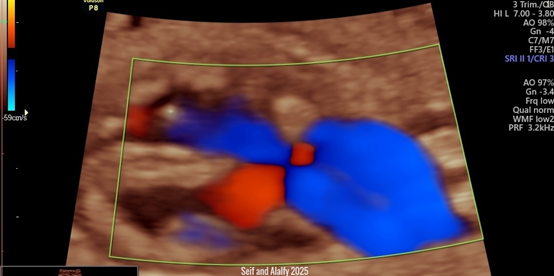

Seif and Alalfy twist sign, this technique describes an oblique view that illustrates the right and left ventricles with the interventricular septum and the atrioventricular valves with the aorta and pulmonary arteries crossing eachothers and till they form the v-sign ending to the ductus arteriosus as seen in Figure 1 and Figure 2.

Figure 1 Shows 2D US with Color Doppler illustrating Seif and Alalfy twist sign ,this technique describes an oblique view that illustrates the right and left ventricles with the interventricular septum and the atrioventricular valves with the aorta and pulmonary arteries crossing each others and till they form the v-sign ending to the ductus arteriosus.

This sign can be approached by sweeping the probe to get the optimum oblique view in the heart to illustrate right, left ventricles, interventricular septum, atrioventricular valves with the aorta and pulmonary arteries crossing each others.

The Seif and Alalfy twist sign can thus demonstrates a normal four chamber view and outflow tracts and 3 vessel views in a very short time Compared to the illustrated fetal echocardiography.